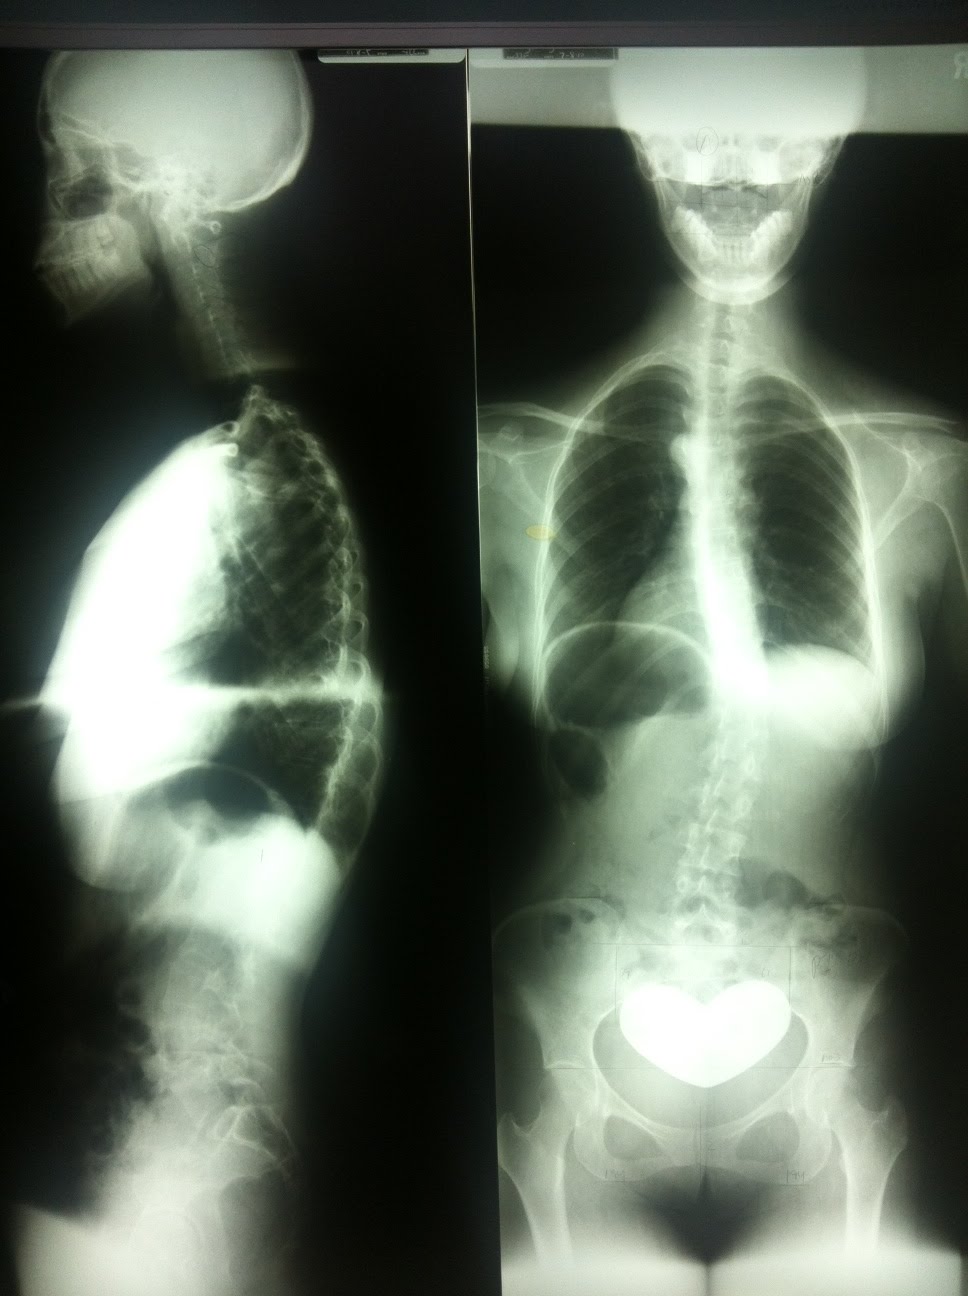

From gonsteadny.blogspot.com

Gonstead New York Wellness Ménière's disease Meniere's Disease X Ray Menière disease is an inner ear problem that manifests with the symptoms of ear fullness, hearing loss, tinnitus, and vertigo attacks. Learn about the classic triad of symptoms (vertigo, tinnitus, and hearing loss) of meniere disease, a condition caused by. This article discusses the role of mr imaging in the diagnosis and management of menière disease, a disorder of the. Meniere's Disease X Ray.